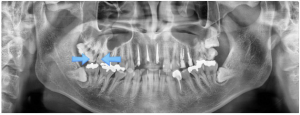

인덕원 인레이치료 잘못되었을 때 어떤 문제가 생길 수 있을까요?

인덕원 인레이치료 잘못되었을 때 어떤 문제가 생길 수 있을까요? 안녕하세요.인덕원 믿음치과 손동근 원장입니다. 치과 치료는 단순히 치료를 받는 것에서 끝나는 것이 아니라, 치료 이후 얼마나 안정적으로 유지되는지도 중요합니다. 특히 충치...